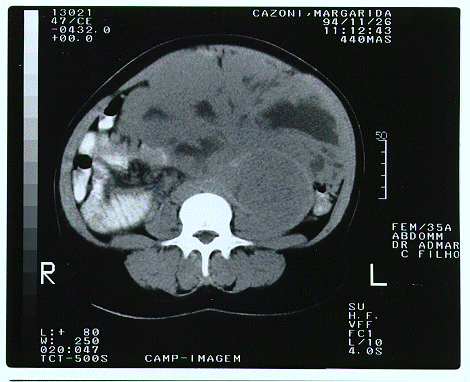

Tomografia computadorizada de abdome(imagem 1 e imagem 2)

Primeira cirurgia

Foi submetida a laparotomia exploradora com achado de tumor extenso retroperitoneal ocupando todo o abdome e rechaçando as estruturas para frente, aderido ao colo transverso e rim E. Foi ressecado

completamente em bloco com o rim E e segmento do colo transverso..